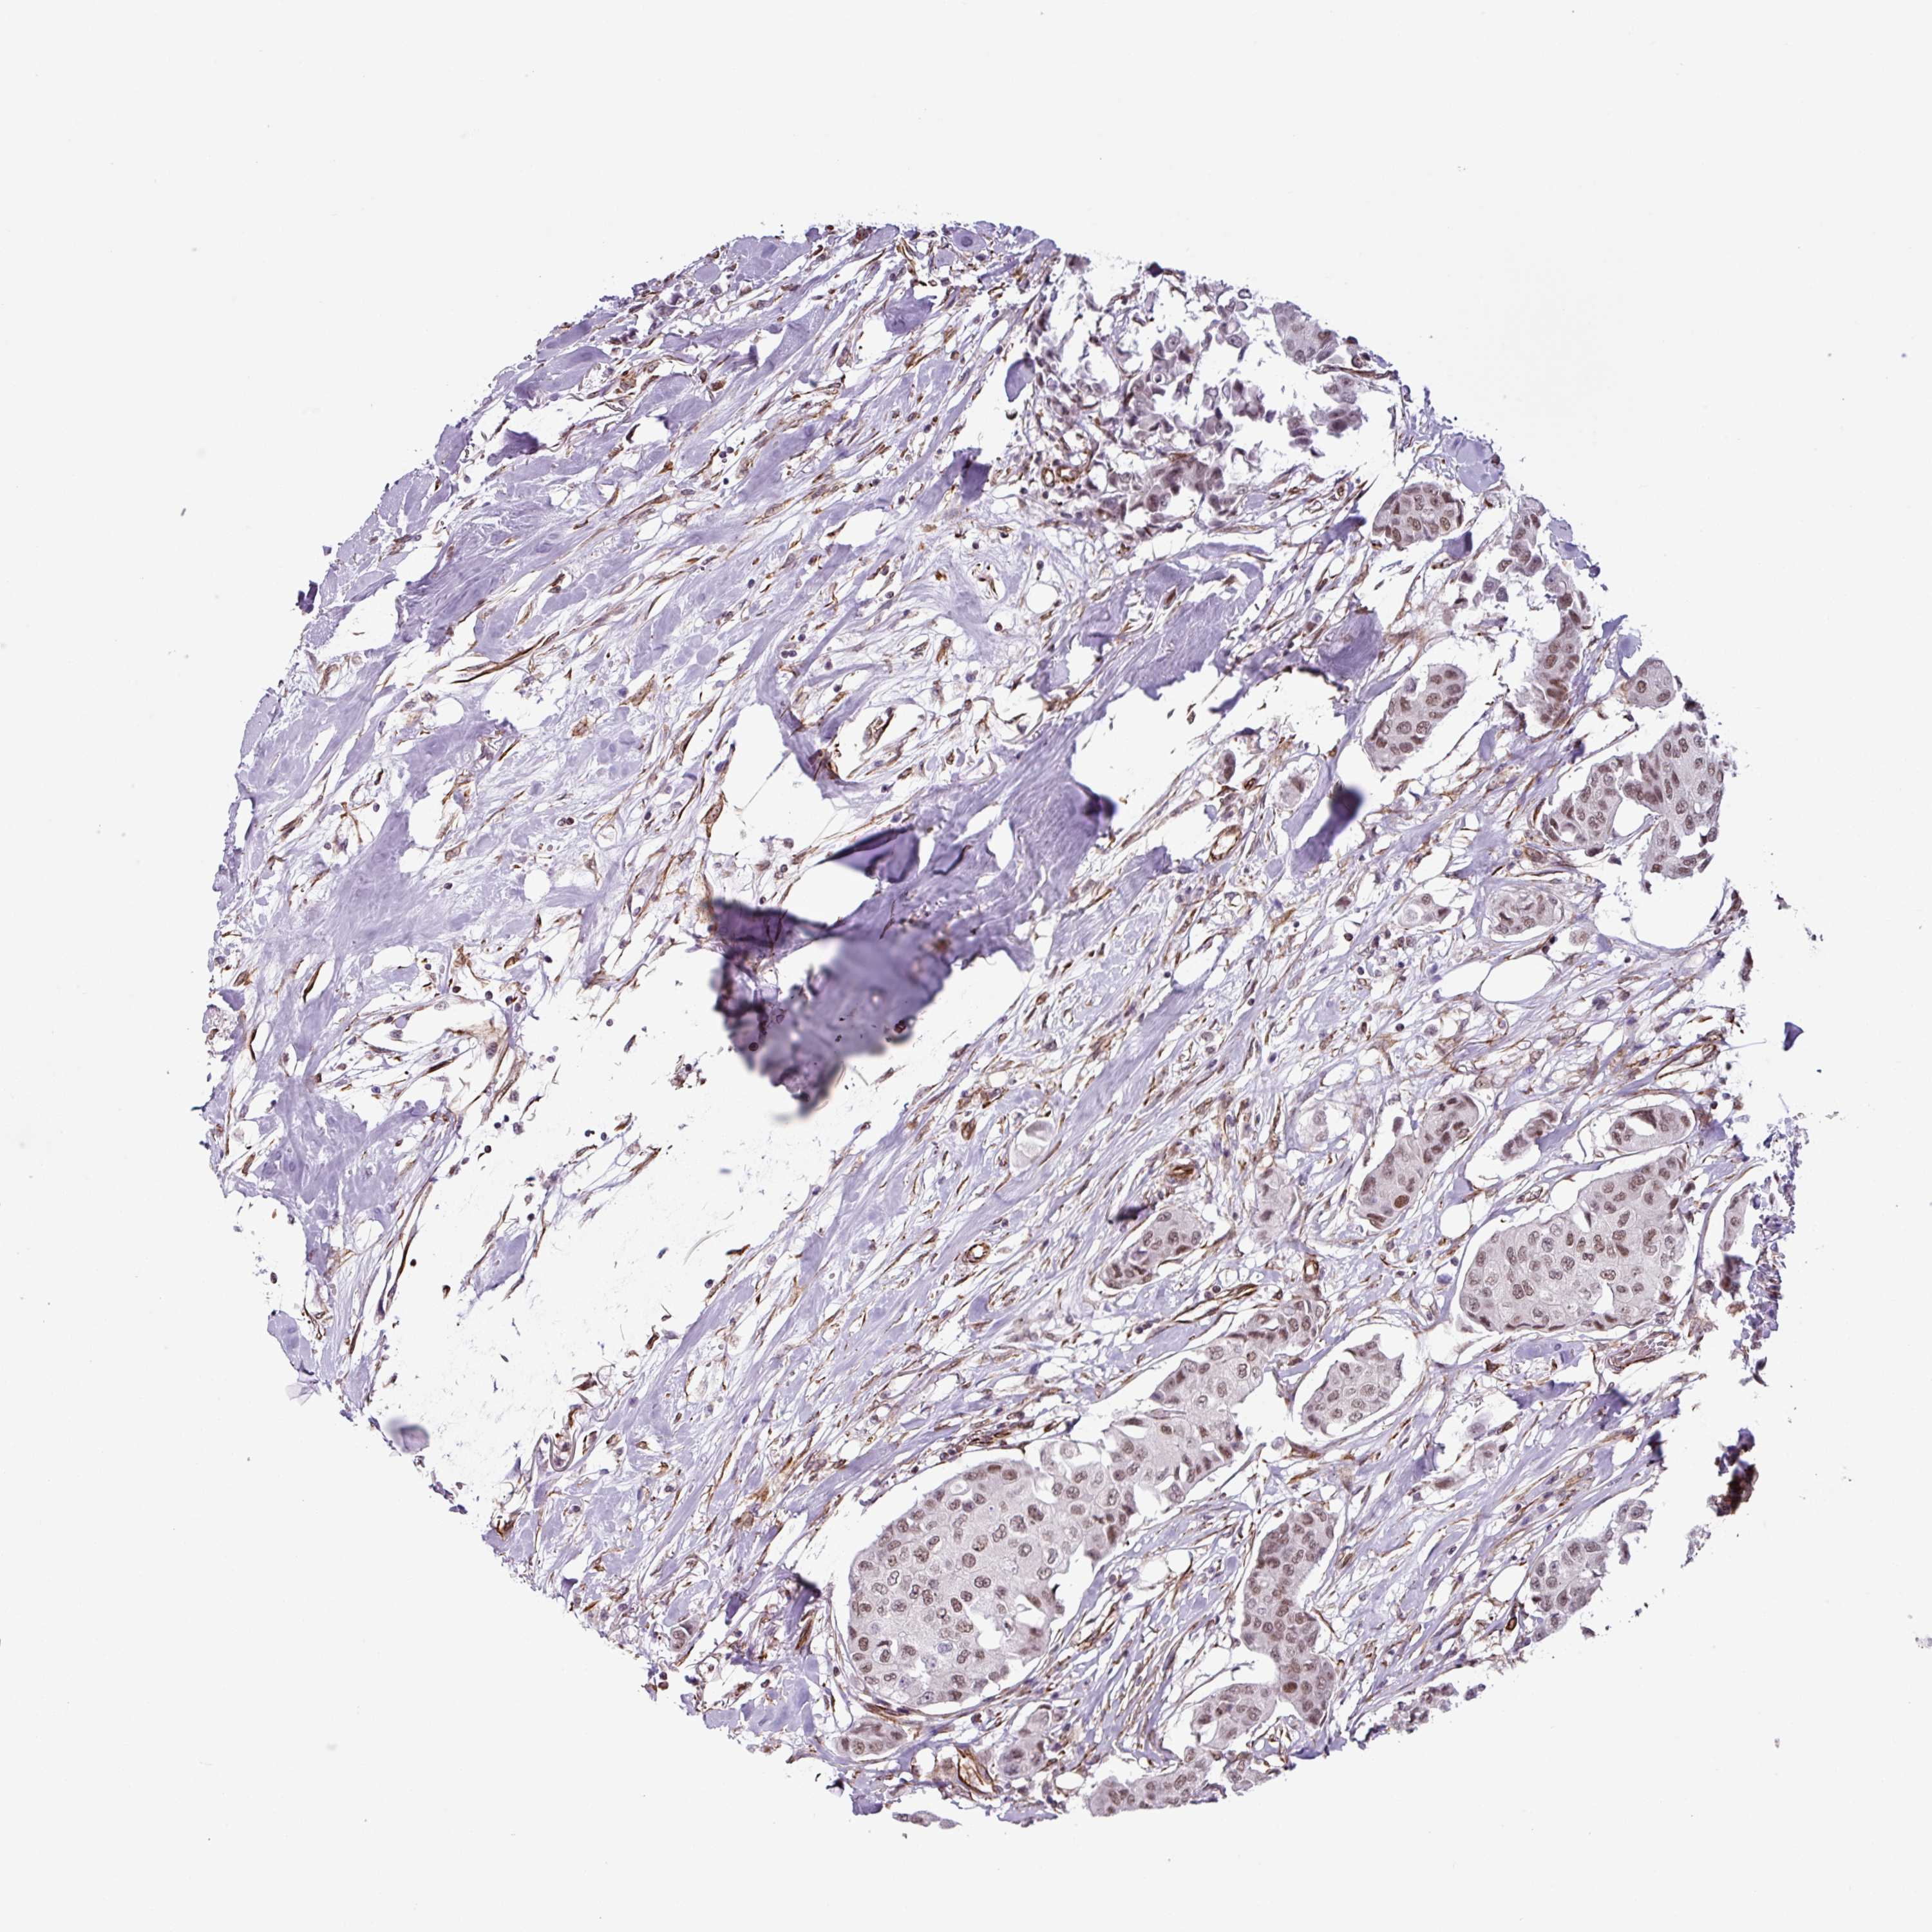

CANCER BREAST CANCER Show tissue menu

BRCA TCGA BRCA VALIDATION PROTEIN EXPRESSION